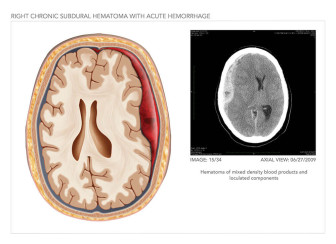

• Interactive

• Slice Chooser®

• Personal Injury

• Traumatic Brain Injury

• Project

• +3